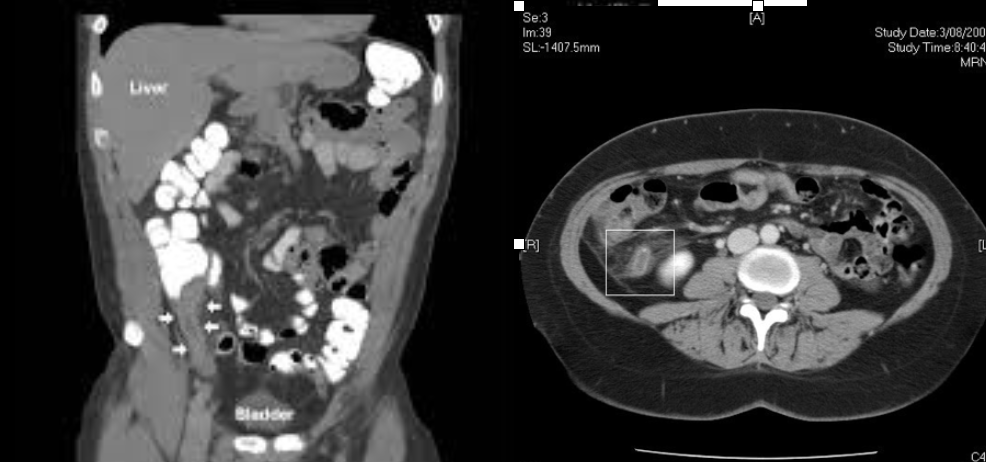

coronal

Which CT view?

Diverticulitis

CT Abdomen/Pelvis IV contrast

Intra-abdominal abscess

CT Abdomen/Pelvis IV contrast

Colonic mass

CT Abdomen/Pelvis IV contrast